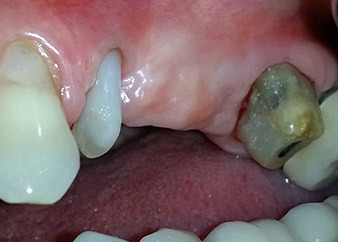

Résultat intermédiaire à deux mois

Les figures 17 et 18 présentent le résultat clinique deux mois après l'intervention chirurgicale. La dent 24 présentait une mobilité réduite, de classe I (Miller) et les tissus mous ne présentaient aucune inflammation. Pour prévenir toute nouvelle infection et pour éviter d'endommager l'attache épithéliale, aucun test n'a été pratiqué à ce stade. Une visite de contrôle a été programmée pour la prochaine incision et la mise en place des parties secondaires de cicatrisation, six mois après l'insertion des implants.

Deux mois après l'intervention chirurgicale

Fig. 17 : Deux mois après l'intervention chirurgicale, la patiente ne ressentait plus aucune douleur et la région ne présentait plus d'inflammation.

après le chirurgie

Fig. 18 : La dent 24 présentait alors une mobilité réduite.

À la consultation des deux mois, la mobilité de l'« élément dentaire » 24 restant était déjà passée de Miller 2 à Miller 1. L'attache des tissus mous était au niveau de la dent voisine 23. De plus, en l'absence de symptômes endodontaux ou parodontaux, son pronostic devra peut-être être révisé.